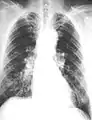

Micrograph of asbestosis showing the characteristic ferruginous bodies and marked interstitial fibrosis (or scarring). H&E stain.

Close-up asbestosis right lower zone ILO 2/2 S/S

The abnormal chest x-ray and its interpretation remain the most important factors in establishing the presence of pulmonary fibrosis.[11] The findings usually appear as small, irregular parenchymal opacities, primarily in the lung bases. Using the ILO Classification system, "s", "t", and/or "u" opacities predominate. CT or high-resolution CT (HRCT) are more sensitive than plain radiography at detecting pulmonary fibrosis (as well as any underlying pleural changes). More than 50% of people affected with asbestosis develop plaques in the parietal pleura, the space between the chest wall and lungs. Once apparent, the radiographic findings in asbestosis may slowly progress or remain static, even in the absence of further asbestos exposure.[25] Rapid progression suggests an alternative diagnosis.

Asbestosis resembles many other diffuse interstitial lung diseases, including other pneumoconiosis. The differential diagnosis includes idiopathic pulmonary fibrosis (IPF), hypersensitivity pneumonitis, sarcoidosis, and others. The presence of pleural plaques may provide supportive evidence of causation by asbestos. Although lung biopsy is usually not necessary, the presence of asbestos bodies in association with pulmonary fibrosis establishes the diagnosis.[26] Conversely, interstitial pulmonary fibrosis in the absence of asbestos bodies is most likely not asbestosis.[11] Asbestos bodies in the absence of fibrosis indicate exposure, not disease.